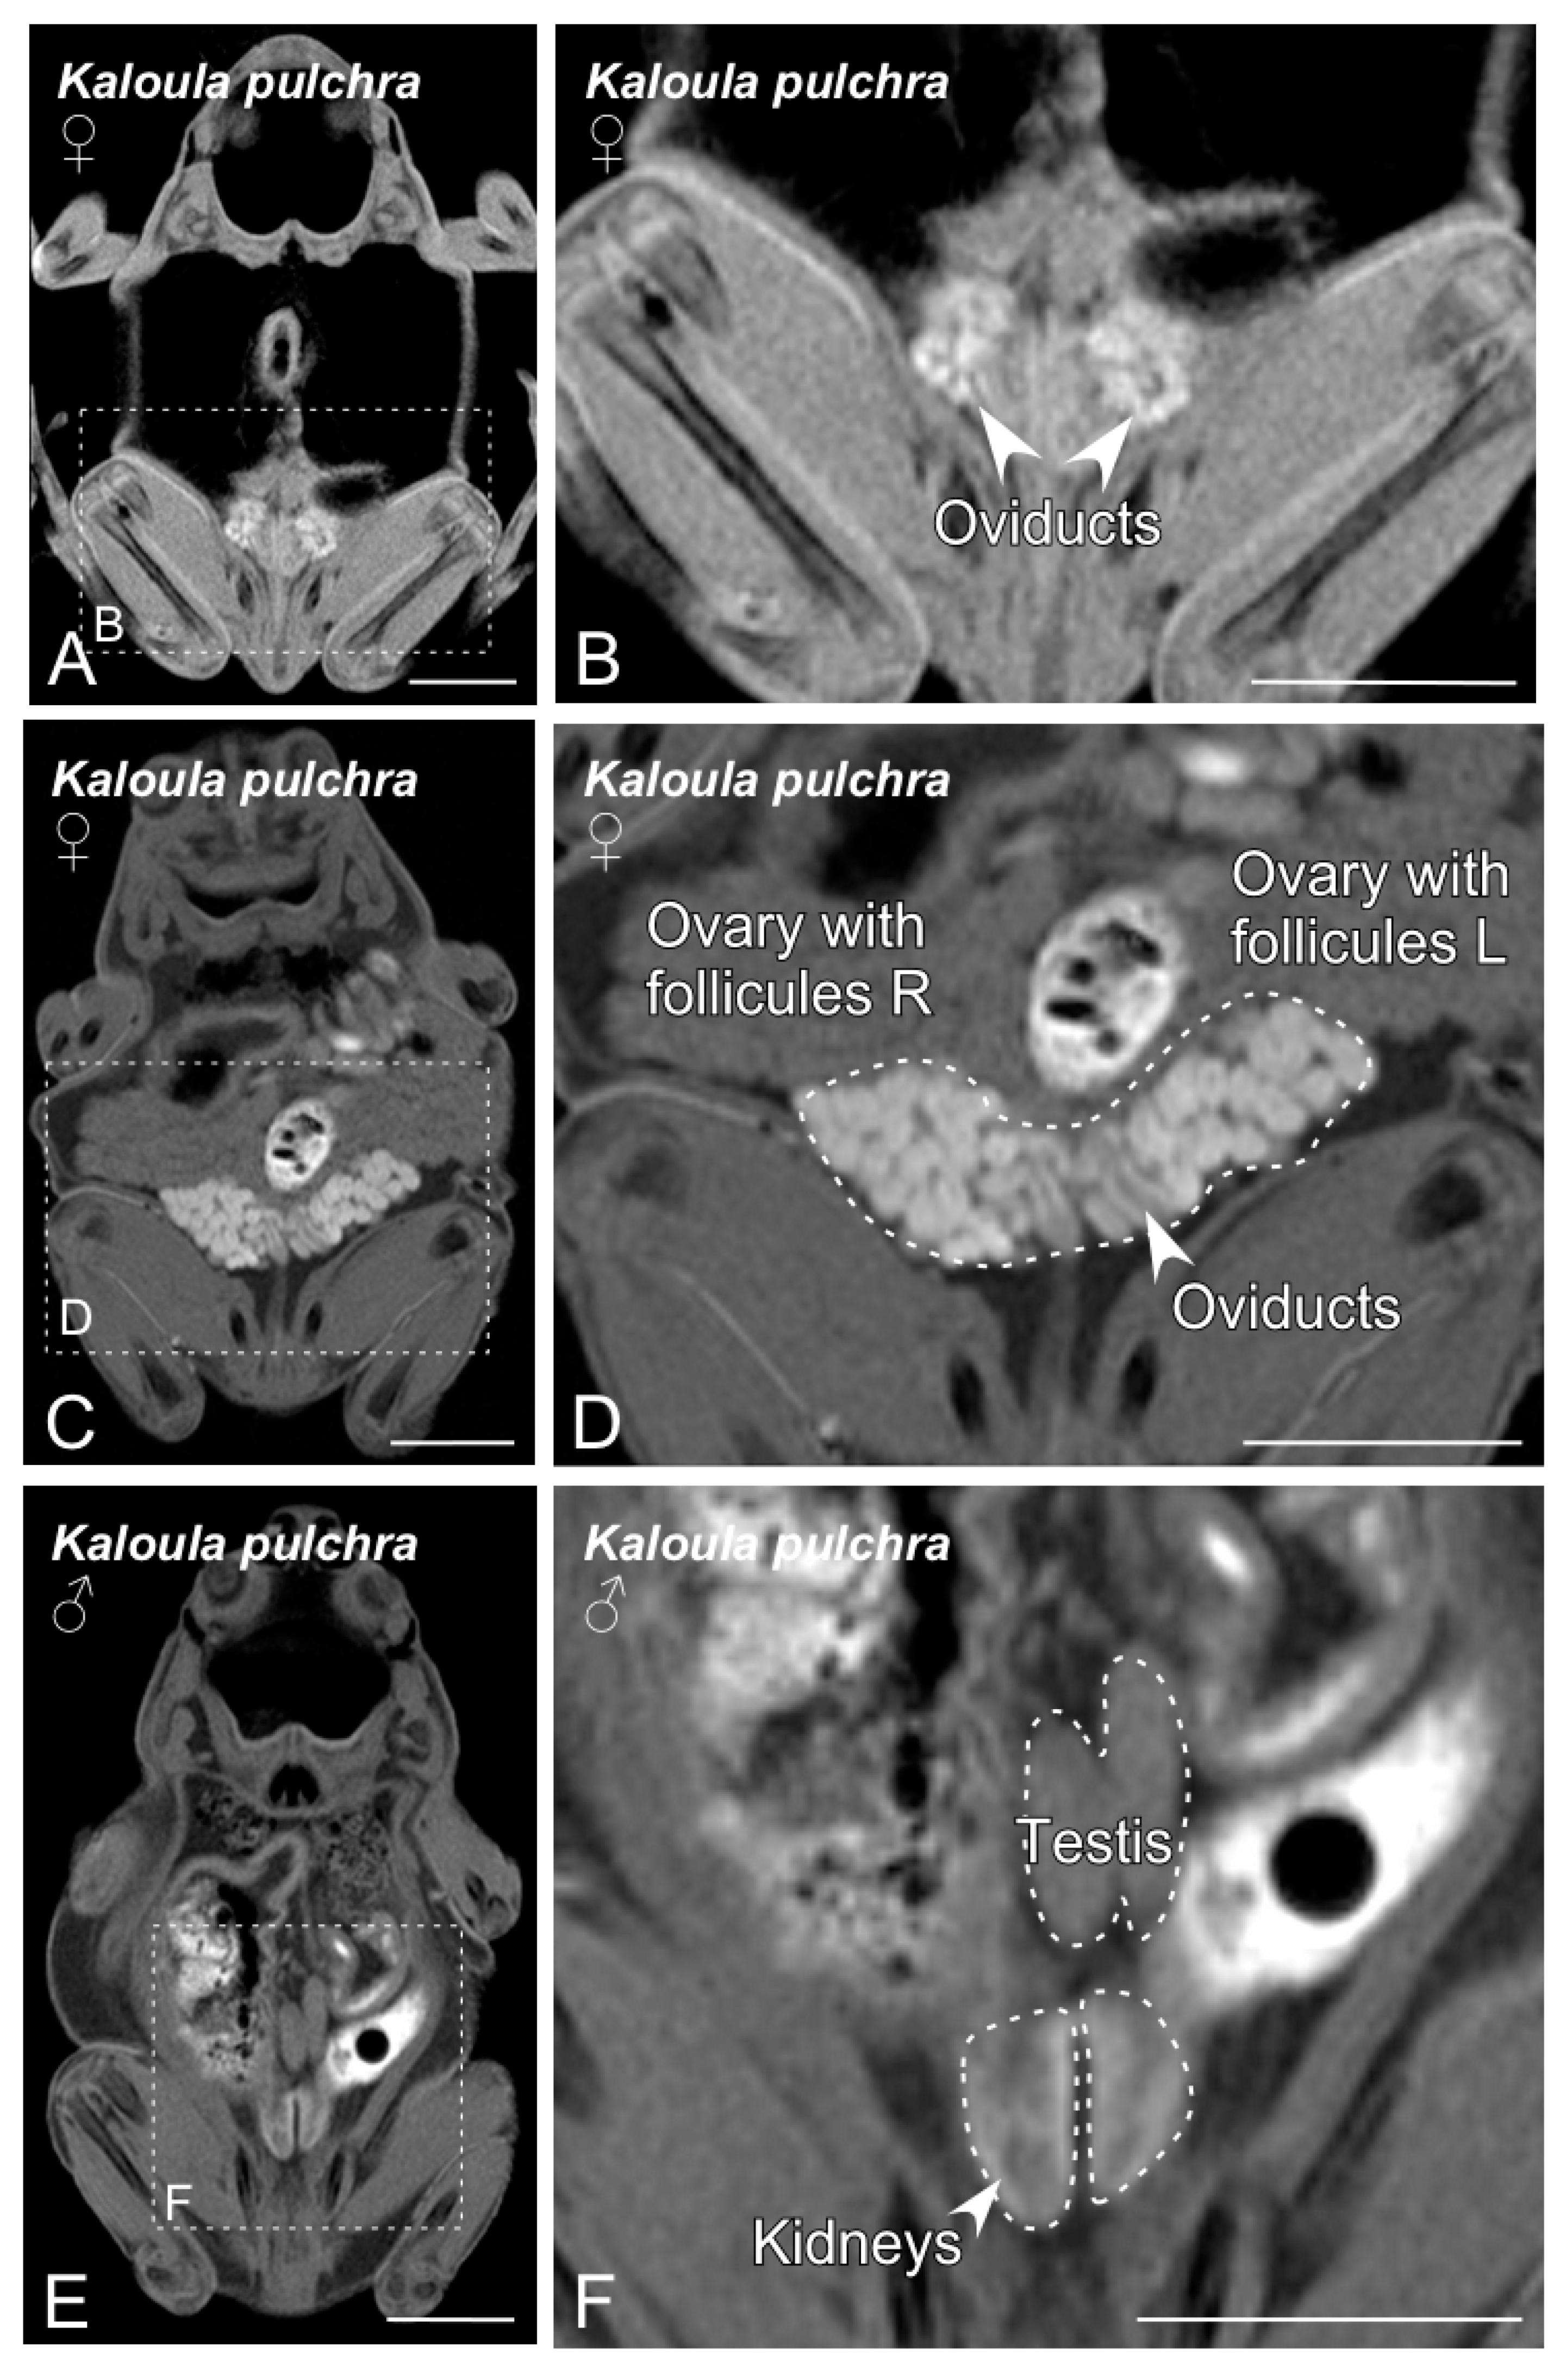

Figure 2. Magnetic resonance imaging (MRI) slices selected to classify Kaloula pulchra anurans by sex. Images from (A) to (D) show the main sexual structures identified in a non-gravid (A,B) and gravid (C,D) Kaloula pulchra female. Images (E) and (F) show testis and kidneys in a Kaloula pulchra male. The dashed lines in (A,C,E) indicate the magnification photos showed in (B,D,F). Scale bars = 1 cm.